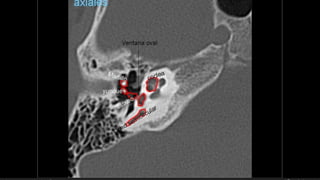

Evaluación Imagenologica

• Ganglio geniculado…66%

• 2da rodilla ……………20%

• Segmento timpánico…8%

• Segmento mastoideo…6%

• #38 Izqu. AXIAL-- fxLongitudinal perdonan la capsula otica (laberinto oseo) Centro AXIAL fx trnasversa lascuales tperdonan el lab erinto oseo Dere: MIXTA – tmp perdona

• #51 IZQ: Canal arqueado(petromastoideo) . Canal SC superior DER: Hiato del facial(blanca), ganglio geniculado (negra)